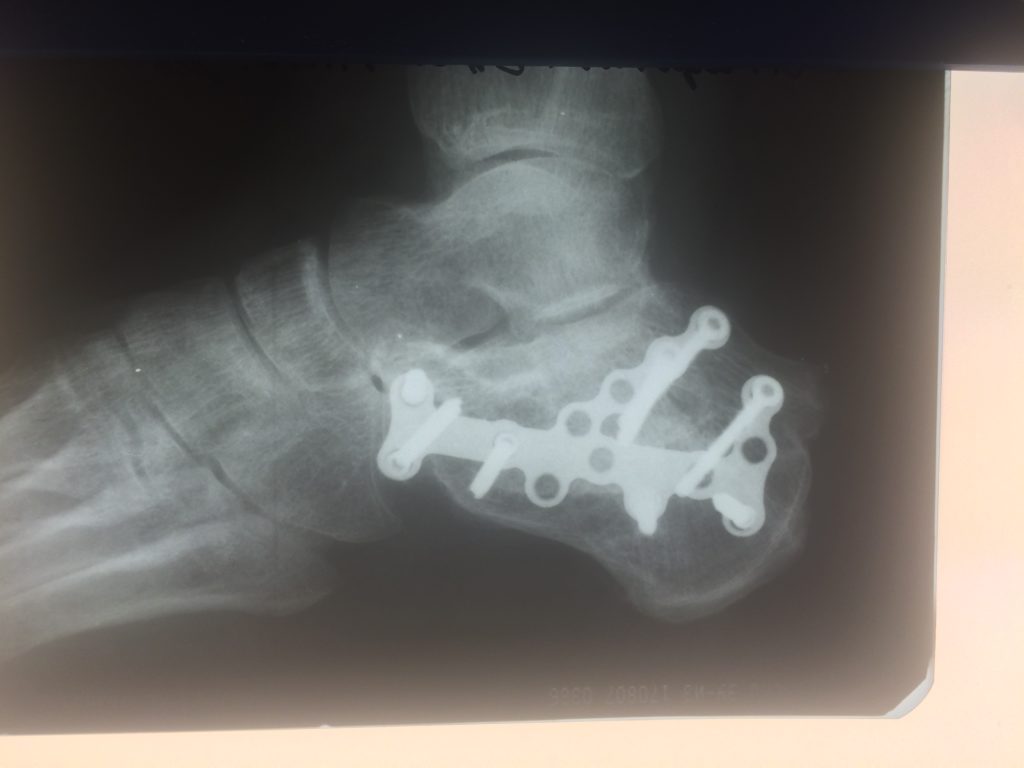

Применение материала Остеоматрикс при импрессионно-оскольчатом переломе пяточной кости

Операция – открытая репозиция, остеосинтез пяточной кости пластиной с костной ксенопластикой материалом «Остеоматрикс». На контрольных снимках в три месяца имеется консолидация перелома, миграции фиксатора нет, имеется остеоинтеграция ксенопластического материала.

Отдаленные результаты через 3 (три) месяца: